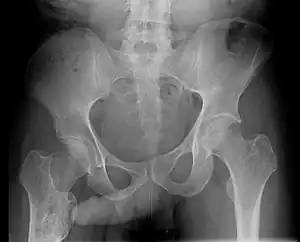

The John Thomas sign,[1] also known as the Throckmorton sign,[2] is a slang or joke term used in the field of radiology. It refers to the position of a penis as it relates to pathology on an X-ray of a pelvis. When the penis (visible on the X-ray as a shadow) points towards the same side as a unilateral medical condition such as a broken bone, this is considered a "positive John Thomas sign," and if the shadow points to the other side, it is a "negative John Thomas sign."[3]

Studies have shown that the "sign" is no better than chance at identifying the location of a hip fracture.[4][5] In those cases where the John Thomas sign is positive, it has been proposed that a person with a displaced hip fracture may try to lie on the injured side to immobilize the fracture and reduce pain; the penis then inclines toward the downward (injured) side.[6]